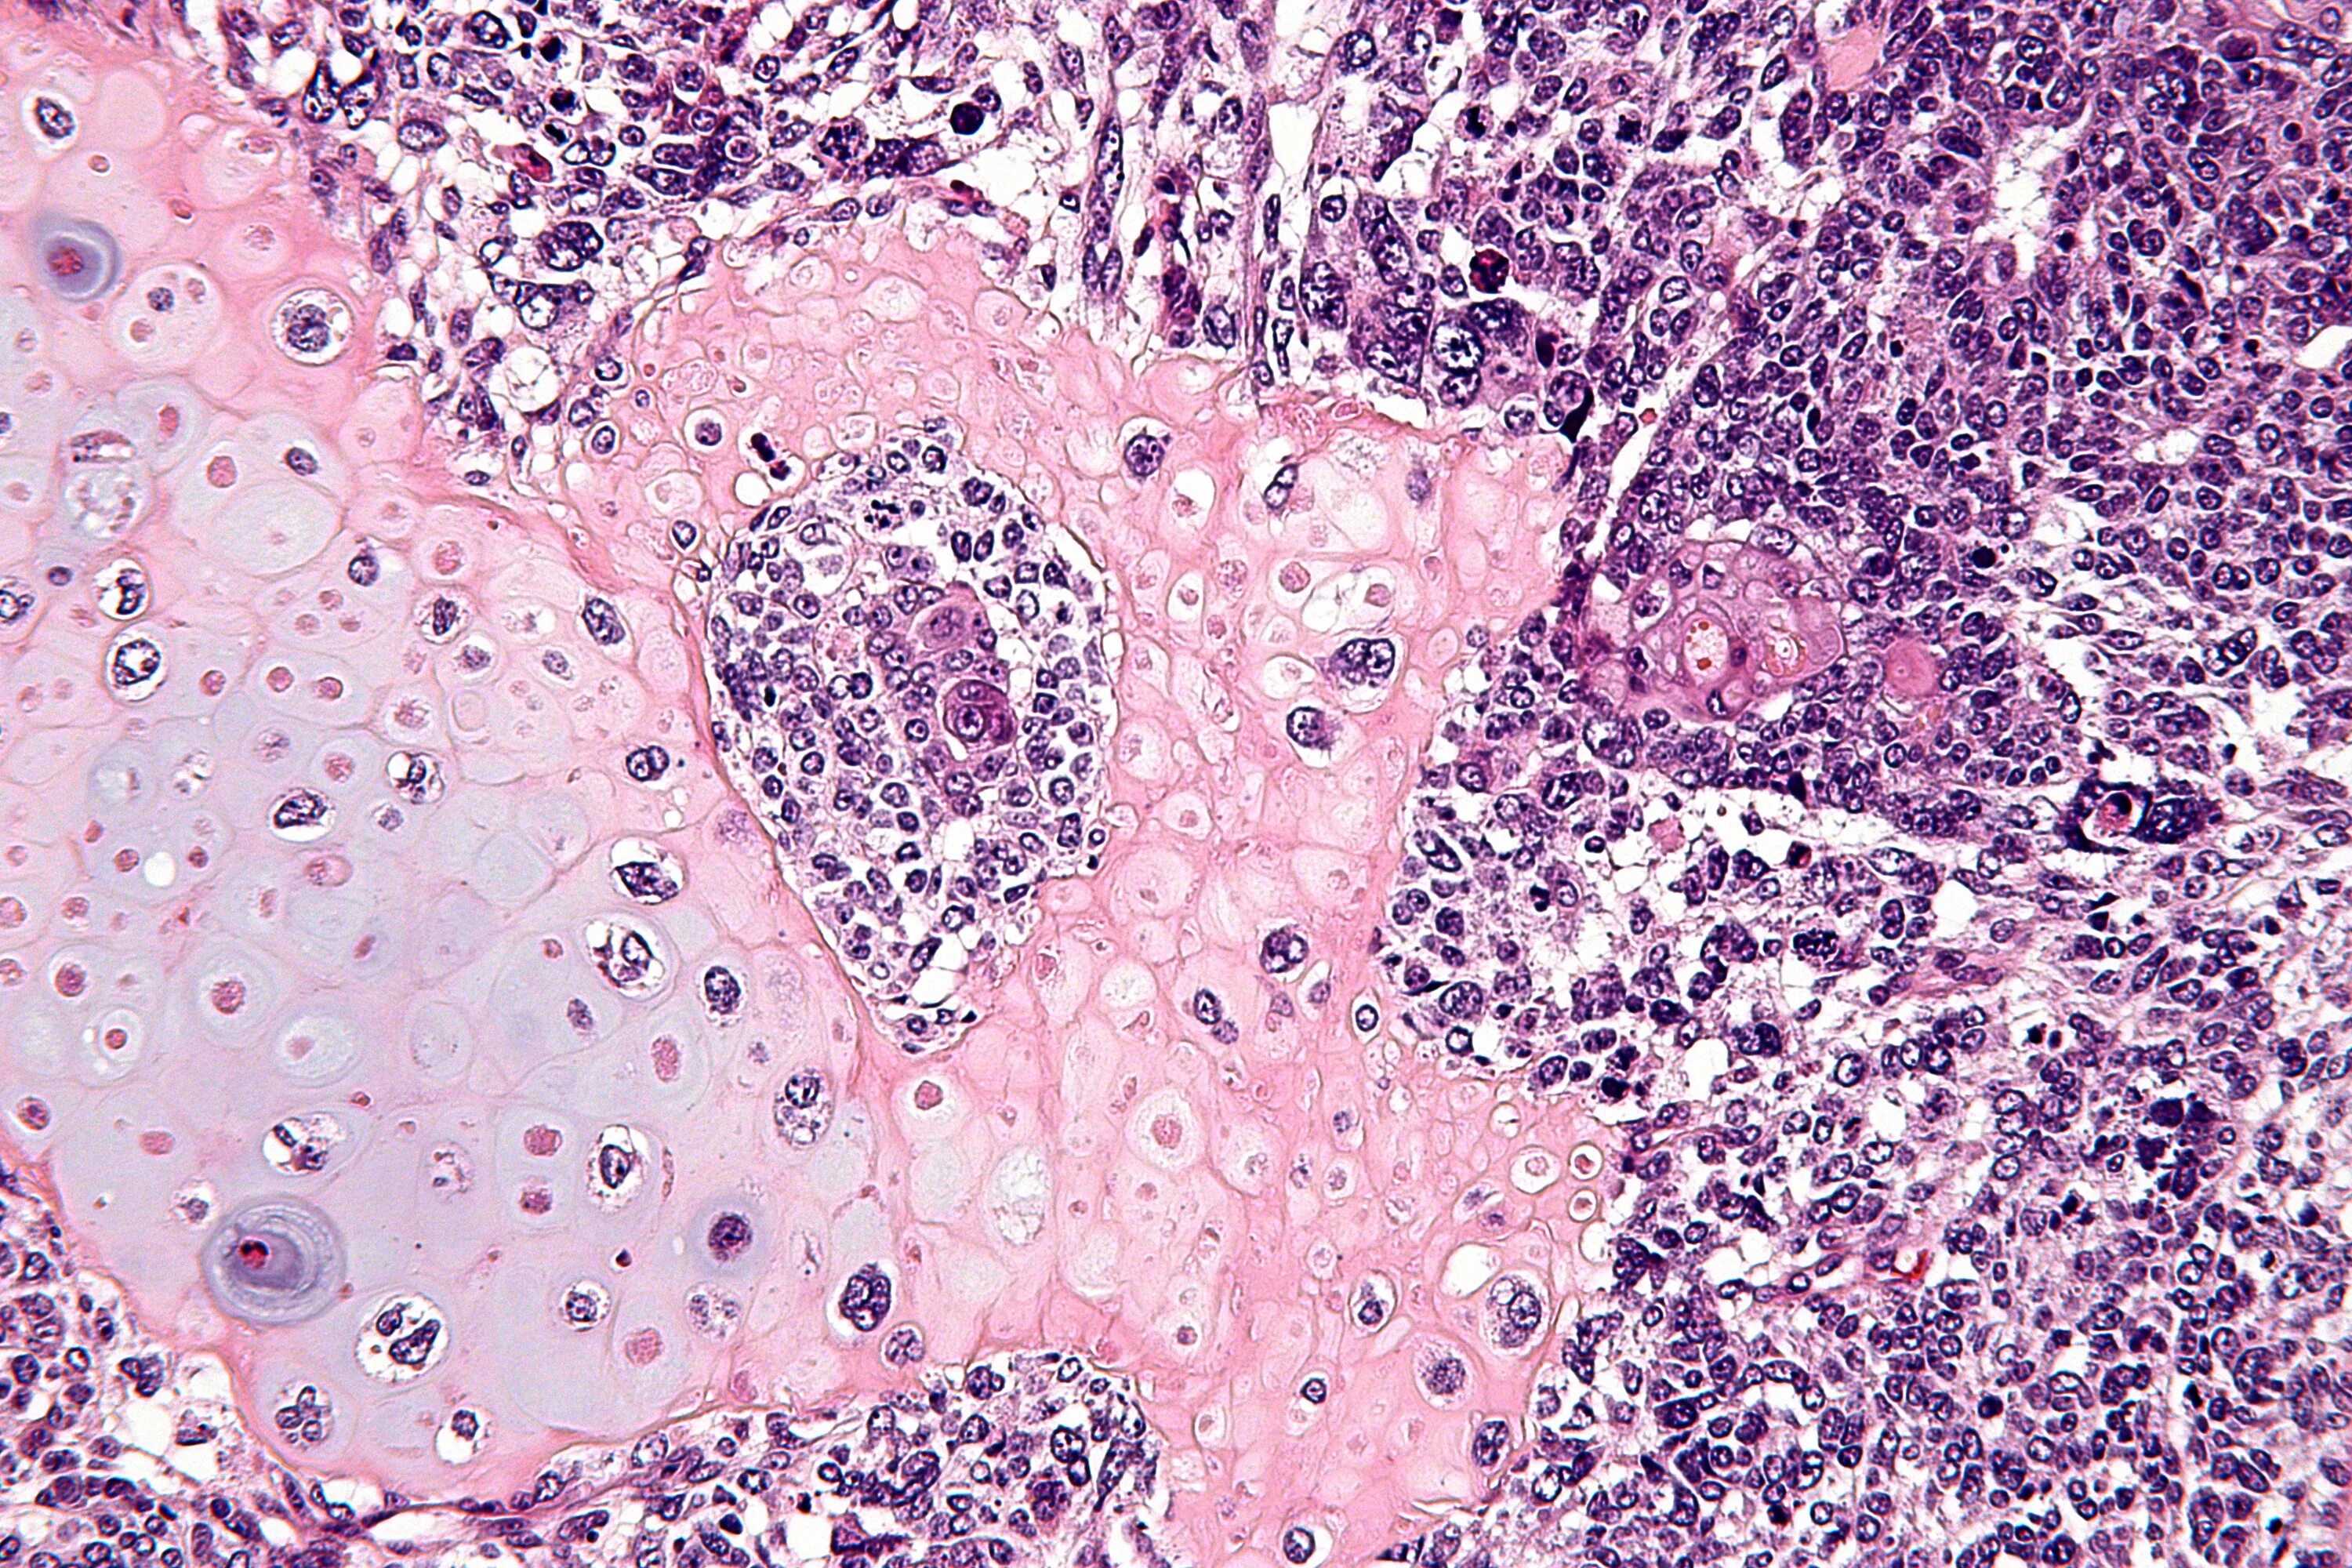

Бластома мозга